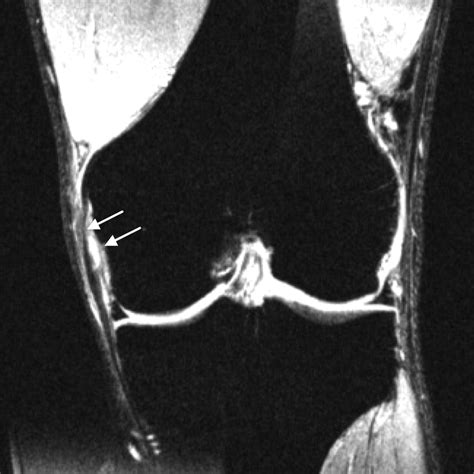

An *Mcl Tear Mri* can help determine the grade of the MCL tear, which is classified as follows:

Grade Description

Grade I Mild tear with minimal damage to the ligament fibers. The knee remains stable.

Grade II Partial tear with more significant damage to the ligament fibers. The knee may feel unstable.

Grade III Complete tear with severe damage to the ligament fibers. The knee is unstable and may require surgical intervention.

An *Mcl Tear Mri* is particularly useful for differentiating between an MCL tear and other knee injuries, such as meniscal tears or anterior cruciate ligament (ACL) injuries. This information is crucial for developing an appropriate treatment plan.